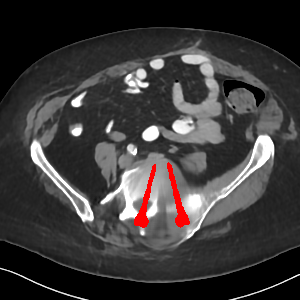

Visual comparison. As shown in Fig. 5, metallic implants such as spinal rods and hip prosthesis cause severe streaky artifacts and metal shadows, which obscure bone structures around them. cGan-CT cannot recover image intensity correctly for both cases. Sinogram domain or dual-domain methods perform much better than cGan-CT. LI, NMAR, and CNNMAR introduce strong secondary artifacts and distort the whole images. In NMAR images, there are fake bone structures around the metals, which is related to segmentation error in the prior image from strong metal artifacts. The segmentation error is also visible in NMAR sinogram. CNNMAR cannot restore the correct bone structures between rods in case 1. The tissues around the metals are over-smoothed in DuDoNet because LI sinogram and image are used as inputs, and the missing information cannot be inferred later. Our model retains more structural information than DuDoNet and generates anatomically more faithful artifact-reduced images.

Visual comparison. Fig. 7 shows two clinical CT images with metal artifacts. Case 1 is with moderate metal artifacts. cGan-CT does not suppress the artifacts completely and generates some fake details. LI, NMAR, CNN-MAR remove all the artifacts but introduce new streak artifacts, which is caused by the discontinuity in the corrected sinogram. DuDoNet outputs over-smoothed sinogram, which leads to blurred tissues close to the metal implants, such as muscle and bone. Only our model can provide realistic enhanced sinogram and remove the artifacts while retaining the structure of nearby tissues. Case 2 is very challenging as the rods bring strong metal shadows and bright artifacts around the vertebra. cGan-CT recovers the shape of vertebra but changes the overall image intensity. Other sinogram inpainting methods fail as the soft tissue and bone near the rods are heavily distorted. Our model removes part of the dark bands and reproduces correct anatomical structures around the rods.